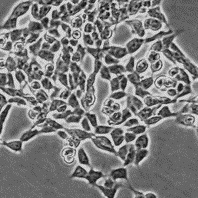

Происхождение: человек, нейробластома

Морфология: фибробласто- и нейробластоподобная

Способ культивирования: монослойный